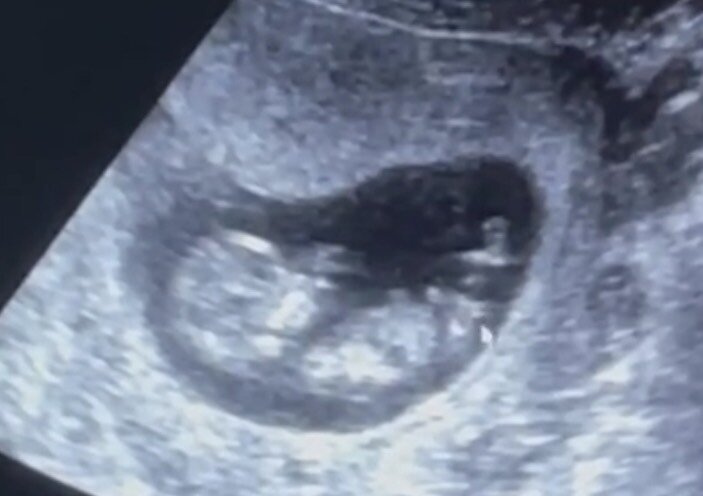

Вот на узи врачу мышкой показывает бугорок и говорит что девочка, до этого за день сказали что больше на мальчика похоже, но типа не точно. Кто знает как так определить, на кого похоже?

Очень похоже на девочку. Бугорок горизонтальный.

Да, он горизонтальный на двух узи этих был

С дочкой также было. В 14 недель видно было